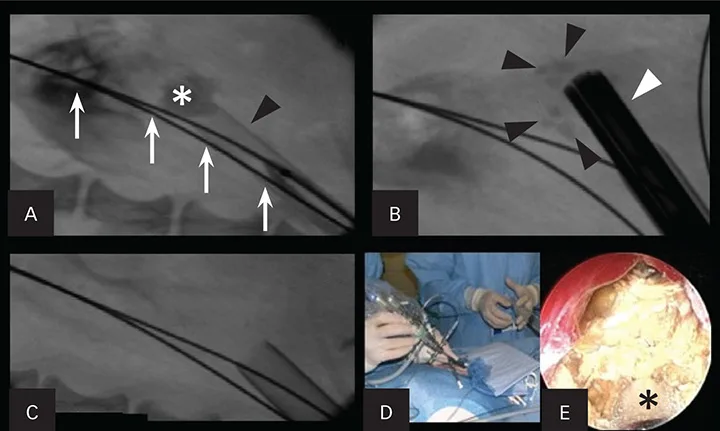

Figure 1. Percutaneous nephrolithotomy in a 3.1-kg female Yorkshire terrier with large nephroliths. Use of a percutaneous access kit under fluoroscopic guidance allows visualization of the large nephrolith (asterisk; A). The access sheath (black arrowhead) is inserted through the renal parenchyma over a dilation balloon. Two safety wires (white arrows) are present. The nephroscope (white arrowhead) is inserted through the sheath onto the stone with a lithotrite, breaking the large stone into fragments (black arrowheads; B). Fluoroscopic image after all stone fragments had been removed from the renal pelvis (C). The nephroscope being placed through the access sheath during percutaneous renal access (D). An endoscopic image of the nephrolith taken during lithotripsy (E). The lithotrite (asterisk) is seen through the working channel of the nephroscope.